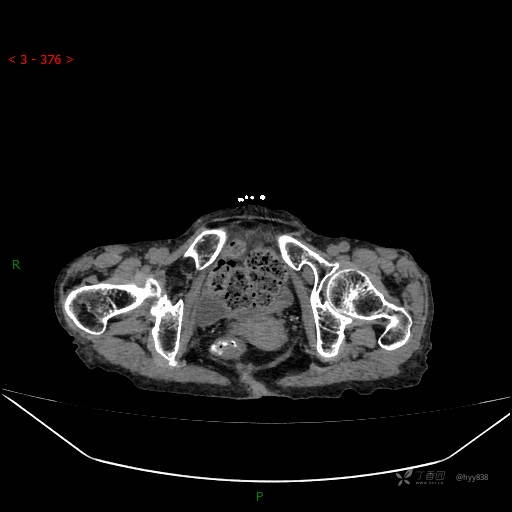

夜班急诊经典病例分享。老年女性,突发腹痛就诊,请讨论……结果公布~

主诉 :腹痛14小时

现病史: 家属诉患者于14小时前出现腹痛,伴有肛门停止排气排便,不伴有畏寒、发热、恶心呕吐、腹泻等不适,患者家属为求进一步治疗,就诊于我院急诊科,门诊以腹痛待查收入院, 起病以来,患者精神、睡眠差,进食少,小便正常,大便未解,近期体力、体重无明显下降。

腹部CT平扫